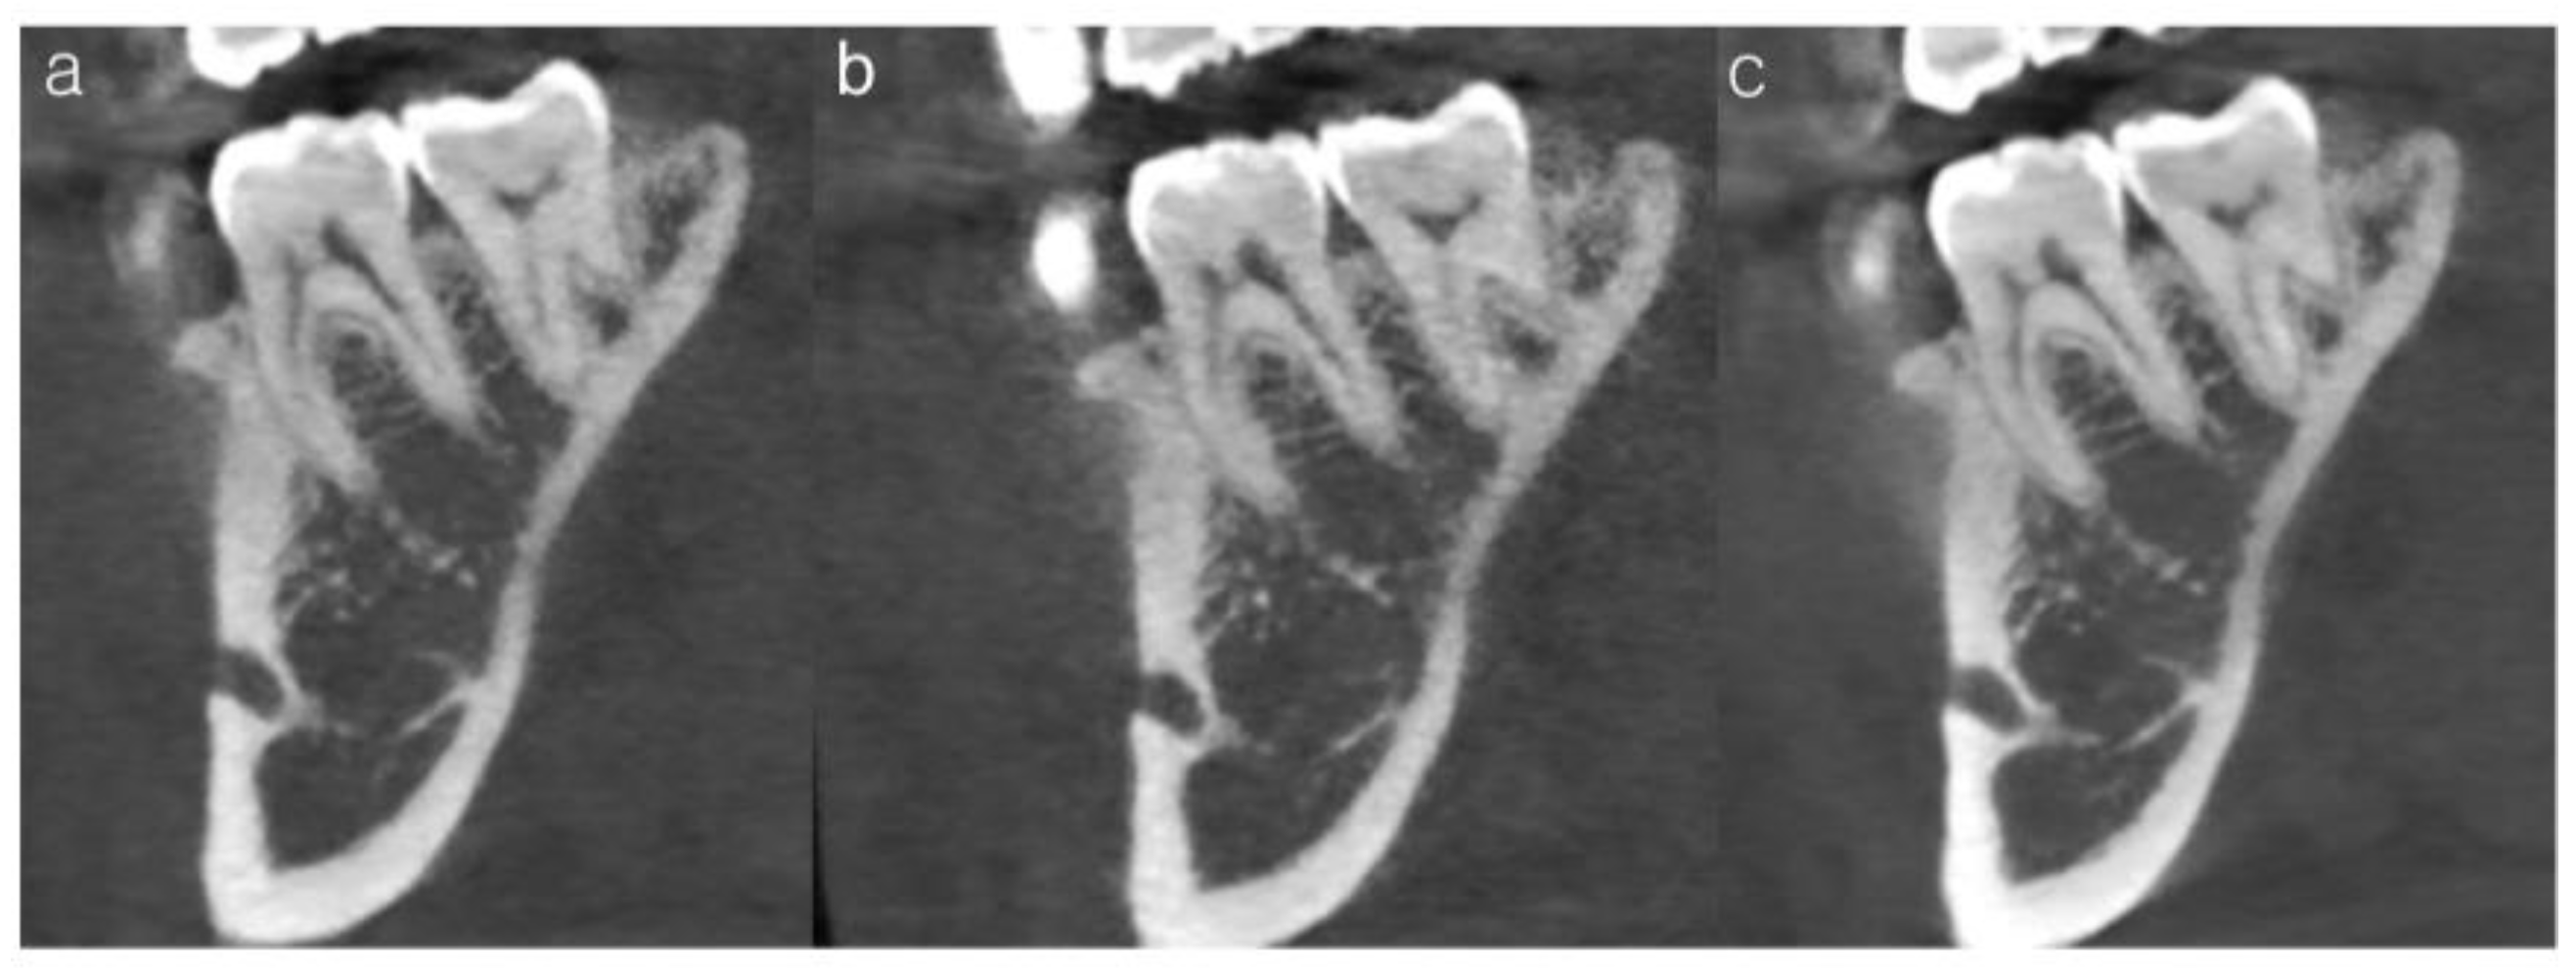

Each criterion was scored on a six-point scale, with higher scores indicating clearer anatomical visualization. All images were independently evaluated in a randomized order, and the evaluators were blinded to both radiation dose level and AI processing status. Each clinician completed the assessment twice, one month apart, to determine intra-rater reliability. Representative examples of insufficient, acceptable, and optimal image quality based on the subjective scoring system are provided in Figure 4.

Figure 4.

Representative CBCT images illustrating subjective image quality ratings for the trabecular pattern of tooth #46. (a) Insufficient image quality (mean score = 3.3), showing poor visualization of the trabecular architecture. (b) Acceptable but suboptimal image quality (mean score = 4.0), in which trabecular structures are partially discernible. (c) Optimal image quality (mean score = 5.1), demonstrating clear and continuous trabecular patterns.